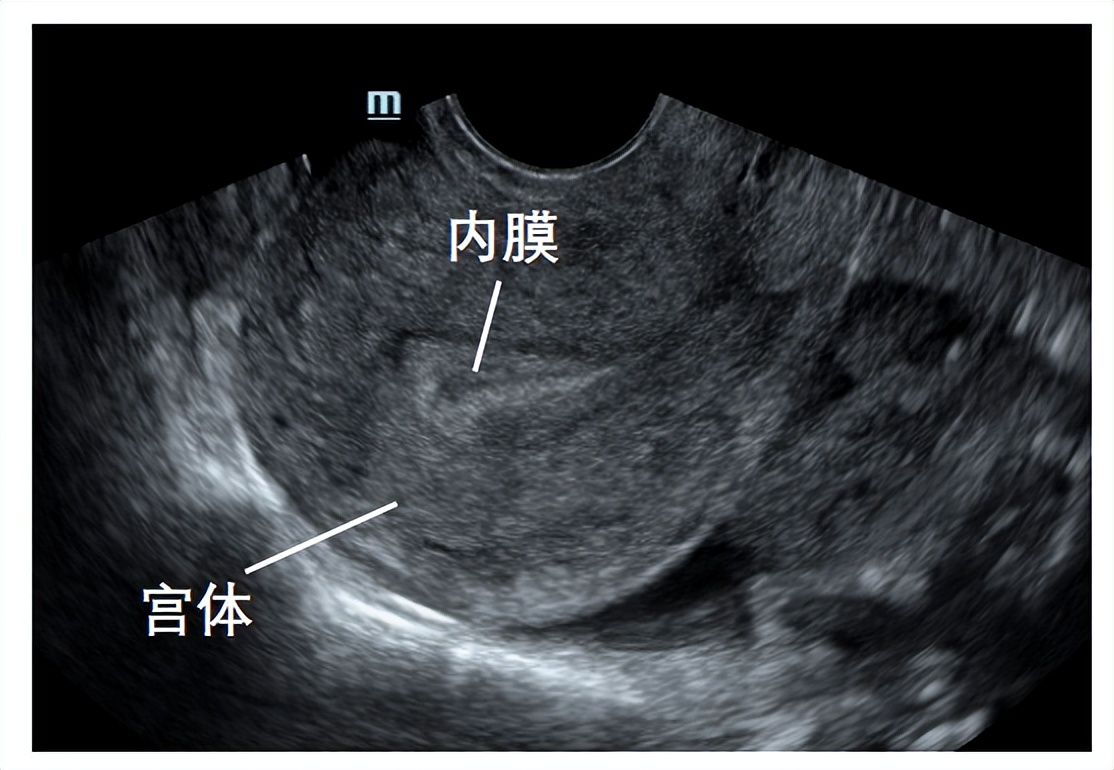

B超监测内膜

卵泡早期的内膜较薄,厚度约3~6 mm,随着卵泡生长,雌激素水平逐渐升高,内膜不断增厚。当卵泡达到成熟时,内膜厚度一般可达10-14mm。我们利用阴道超声根据Gonen分型标准,对内膜形态进行分型,分为三型:A、B、C型。A型及B型子宫内膜的妊娠率显著高于C型。

A型即三线型内膜,外层和中央为强回声线,外层和宫腔中线间为低回声区。常见于子宫内膜增生期。

B型为弱三线型,为均一的中等强回声,宫腔中线回声不明显,一般见于黄体早期。

C型为均质强回声,为均质强回声,无宫腔中线回声,一般见于黄体晚期。